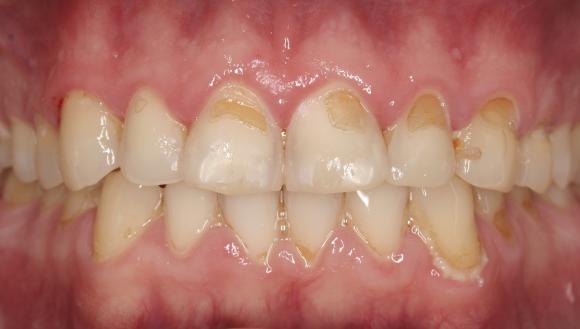

Hammaseroosion merkkejä ovat esimerkiksi hampaiden kuluminen, hammaspintojen himmentyminen, hammaskiilteen alla olevan hammasluun paljastuminen, etuhampaiden kärkien rispaantuminen ja hampaiden vihlominen. Hampaisiin voi tulla laakeita kuoppia (kuten kuvassa alla), ja hampaissa olevat paikat voivat jäädä kiilteen liukenemisen vuoksi hampaan pinnasta koholle (kuten alemmassa kuvassa).

Hammaseroosio laakeita kuoppia